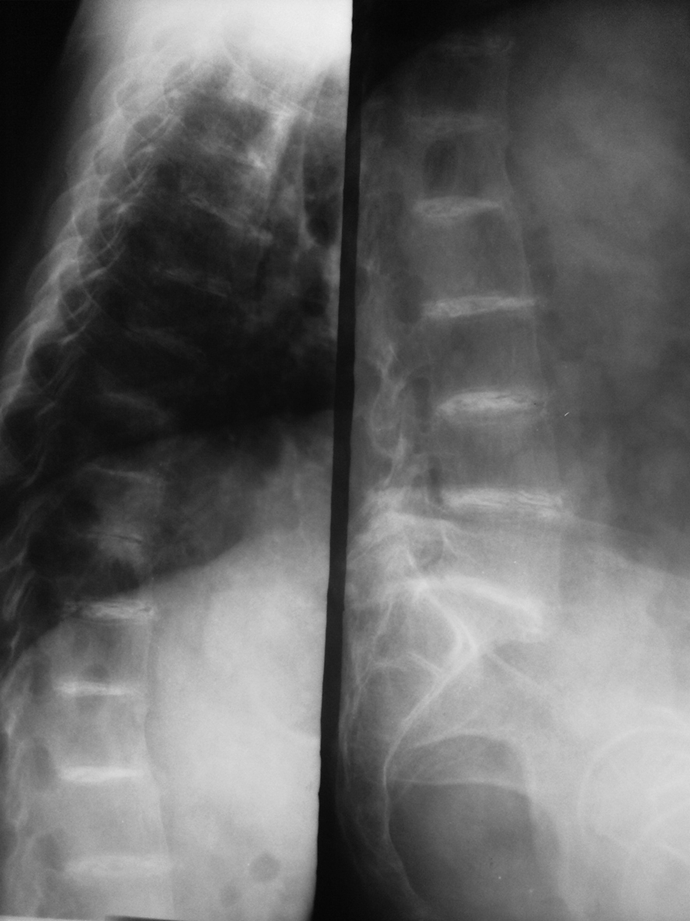

Patient with this disease complains of back pain. His wife complains that his ears are blue.

What is ochronosis?